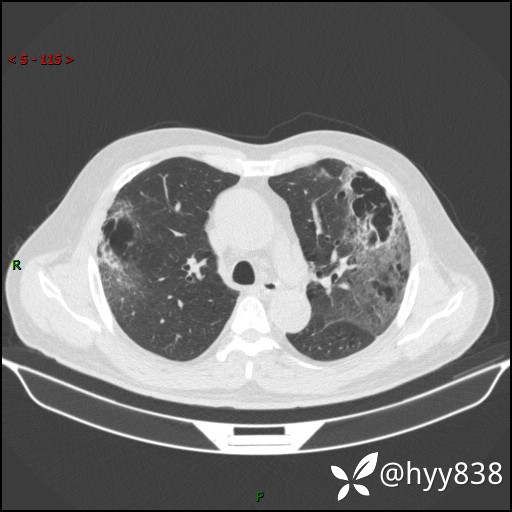

一周后胸部CT